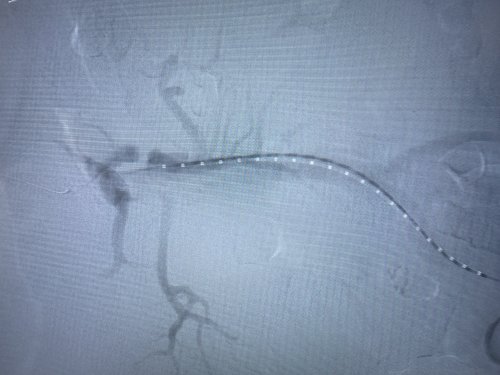

由于患者手术情况复杂,血管外科团队与介入导管室、麻醉科等积极沟通并进行充分的手术准备,在多学科相互配合下,为患者行腹主动脉覆膜支架置入及“四开窗”术,手术顺利,完美隔绝夹层破口,保留腹腔干、肠系膜上动脉、双肾动脉,患者恢复良好。

据市第二人民医院血管外科主任、副主任医师、阜阳市医学会外科学分会血管外科学组组长、血管外科学科带头人芮清峰介绍,累及内脏动脉的主动脉瘤或主动脉夹层一直是治疗的难点,传统外科开放手术,创伤大、并发症多、死亡率高。随着微创技术的发展,主动脉腔内修复已成为主动脉疾病的主流治疗方式,微创、并发症少;但是累及内脏动脉的纯腔内治疗(开窗支架或分支支架技术)操作复杂,依照分支血管位置,在支架上开出对应的"窗口",个体化设计支架,在隔绝主动脉瘤或夹层的同时,避免了分支血管缺血。应用开窗型带膜支架,术中使支架上的孔道与分支血管相对,既能避免封堵重要血管,又可获得足够的封堵区域。